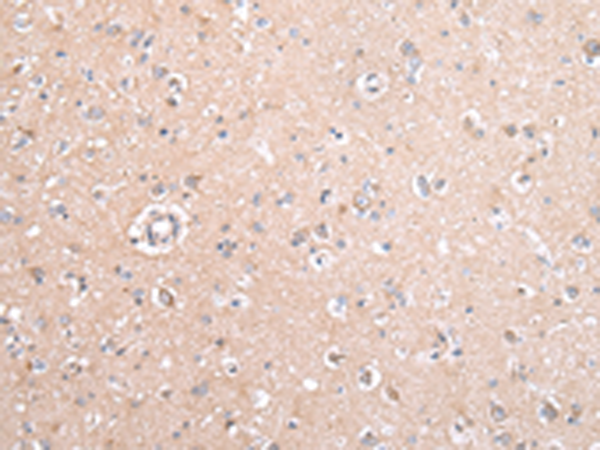

分类: 科研抗体货号: P12454别名: FECD; PPCD; FECD1; PPCD2应用: IHC反应种属: Human, Mouse